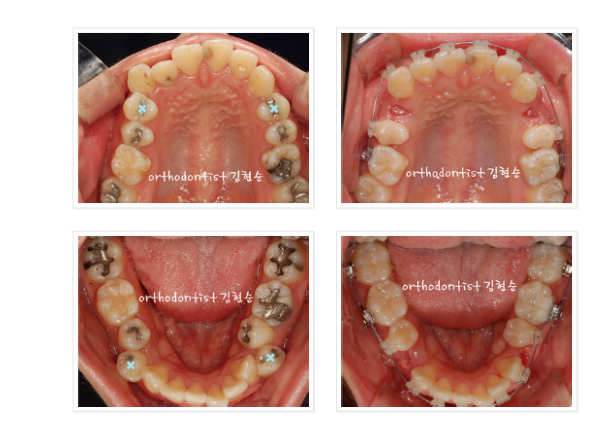

위아래 사진의

하늘색 X 표시 보이시나요?

송곳니 바로 뒷편의 치아인

작은 어금니를

윗쪽 2개, 아래쪽 2개

총 4개를 먼저 발치합니다.

그리고 위아래 사진처럼

치아를 발치한 빈 공간으로

치아를 재배열하며

앞니도 뒷쪽으로

밀어넣기 위해

윗쪽 잇몸에

미니 스크류(MIni Screw)를

심고, 미니스크류를 이용해

치아 바깥쪽에서

앞니를 안으로

이동시키는 힘을

가중시켰습니다.